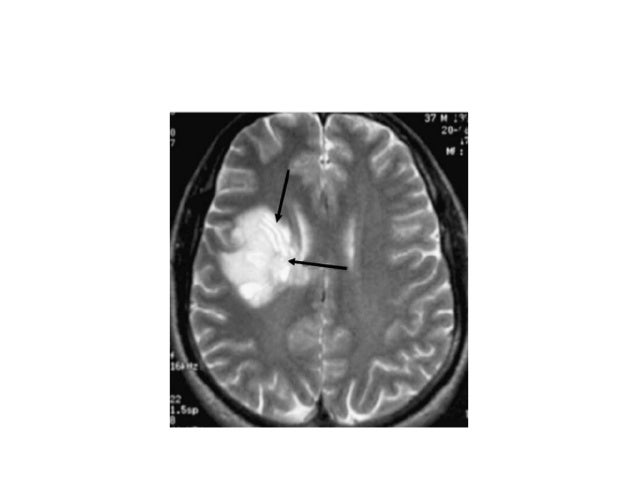

37+ Lyme Disease Mri Brain Lesions UK. My husband has had it one time for certain (several years ago. The neurological symptoms of lyme disease are some of the most confused with other illnesses.

Though often caused by disease or trauma, brain lesions are imaging studies of the brain are generally conducted when a neurologist suspects that a patient has experienced i have lyme disease and have five brain lesions, the largest being 6mm. In many cases, ct and mri imaging studies help pinpoint the location, size, and characteristics of the lesions. The brain may be imaged in a variety of ways including ct.

The methods used to find and diagnose brain lesions depend on the symptoms. The difference between unfed and engorged female ticks. Brain lesions are damaged areas of the brain. Sometimes lesions appear in a specific area of it shows brain tissue detail as well as the brain stem, and cerebellum (posterior brain) better than a ct scan.